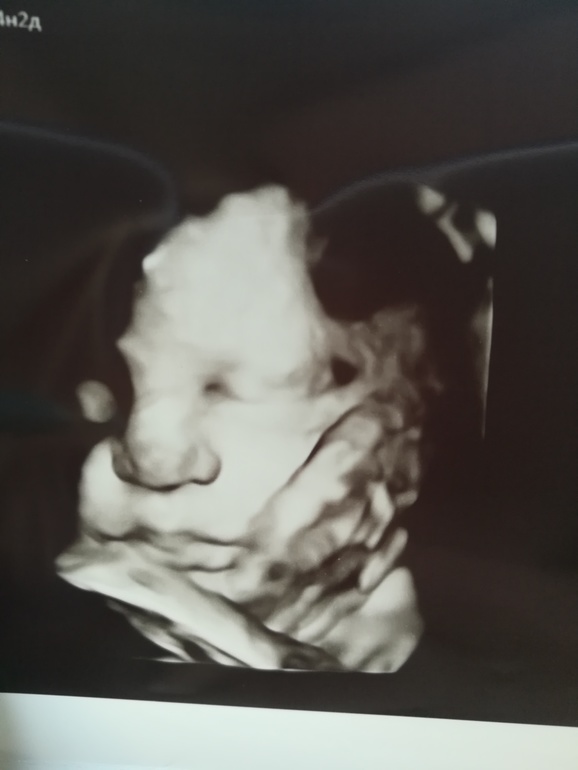

Урааа наконец то сделали третий скрининг и увиделись с дочуркой, нам так долго её показывали в трехмерной проекции, что мы вместе с врачом-диагностом обсудили на кого же она похожа))

Вес 2486 , двойное обвитие, единственное, что плохо по УЗИ. В ЖК врач сказала сделаем в 37 недель на их древнем аппарате, посмотрим будет ли обвитие.

И прикрепляю фото с УЗИ и животика